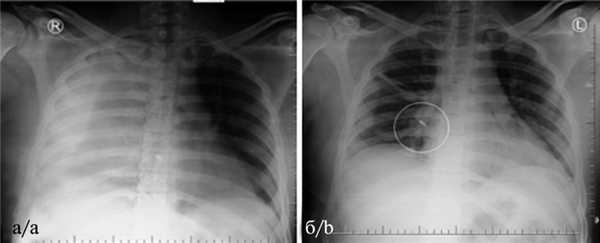

Пациент У., 23 лет, поступил 19.03.18 через 1 ч после полученного на улице ранения из пневматического оружия. Состояние при поступлении средней тяжести. Кожный покров бледной окраски, влажный. Аускультативно в легких везикулярное дыхание, значительно ослабленное справа. Насыщение крови кислородом 96%. ЧДД 20 в минуту, ЧСС 100 в минуту. АД 90/70 мм рт.ст., ШИА 1,11. На коже передней грудной стенки в пятом межреберье справа по краю грудины звездчатая рана диаметром около 0,4 см, с незначительным кровотечением. При УЗИ плевральных полостей в положении лежа выявлен правосторонний гидроторакс с разобщением листков плевры до 2,3 см. На обзорной рентгенограмме груди в прямой проекции правое легочное поле гомогенно интенсивно затенено на всем протяжении по причине гемоторакса. В проекции ThVIII определяется нечеткая тень неправильной формы (рис. 3, а). Рис. 3. Ранение правой половины груди из пневматического оружия у пациента У. а — равномерное среднеинтенсивное затенение правого гемиторакса (гемоторакс 2500 мл), нечеткая тень инородного тела в проекции ThVIII; б — инородное тело в проекции корня правого легкого — деформированная расширительная пуля от пневматического оружия (обведена). Левое легочное поле прозрачное, тень средостения смещена влево.

На послеоперационной обзорной рентгенограмме в проекции IV сегмента легкого выявлена тень инородного тела — сильно деформированной свинцовой расширительной пули от пневматического оружия (см. рис. 3, б). Послеоперационный период протекал с явлениями травматического экссудативного плеврита. Выполнена однократная плевральная пункция, при которой эвакуировано 300 мл серозной жидкости. Состояние пациента улучшилось, и на 13-е сутки после операции он был выписан на амбулаторное долечивание в удовлетворительном состоянии.